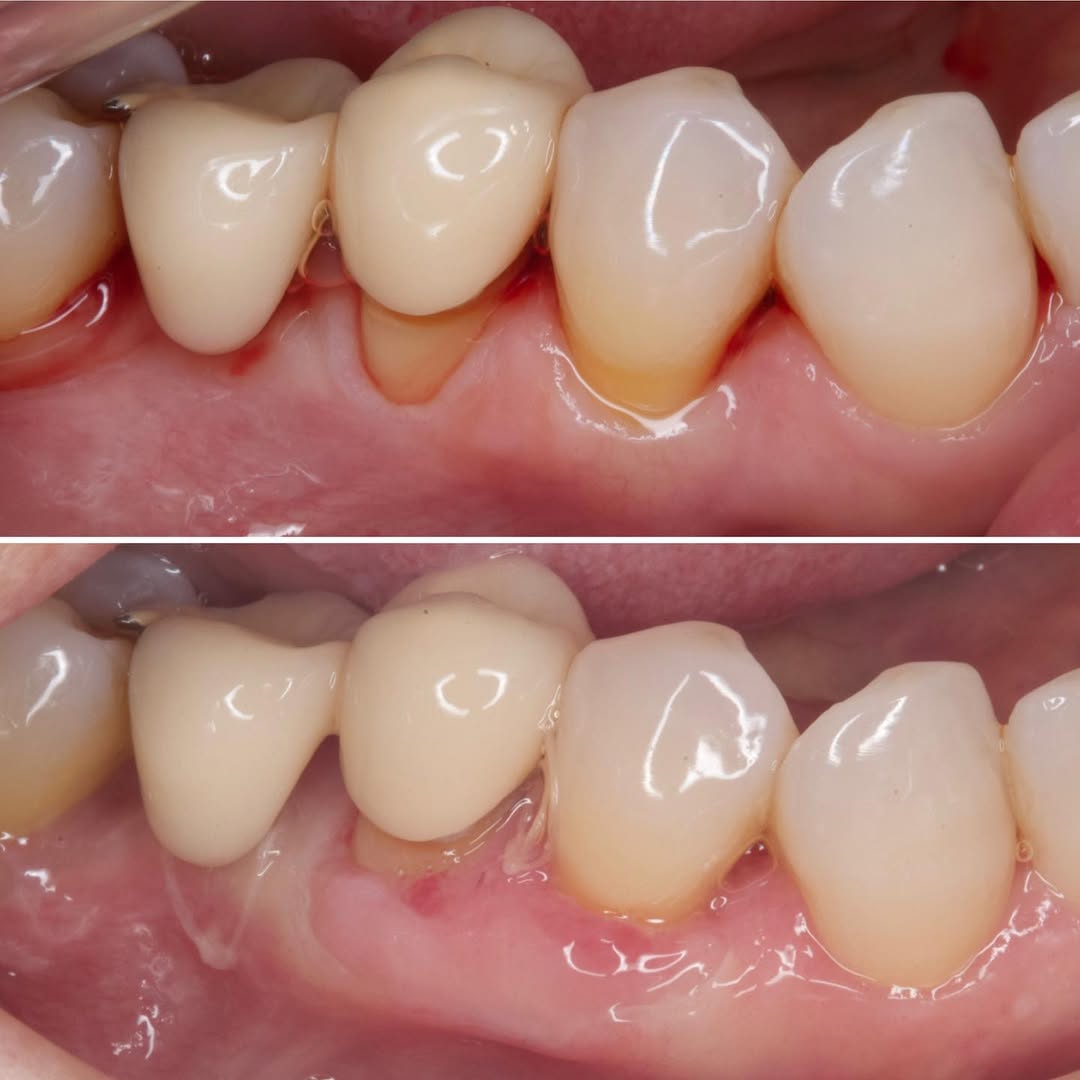

Podrás asistir a la planificación de casos y cirugía de injerto de tejido conectivo. Factores determinantes y elección de la técnica adecuada. Sumérgete en un protocolo predecible y técnicamente correcto para obtener resultados óptimos.